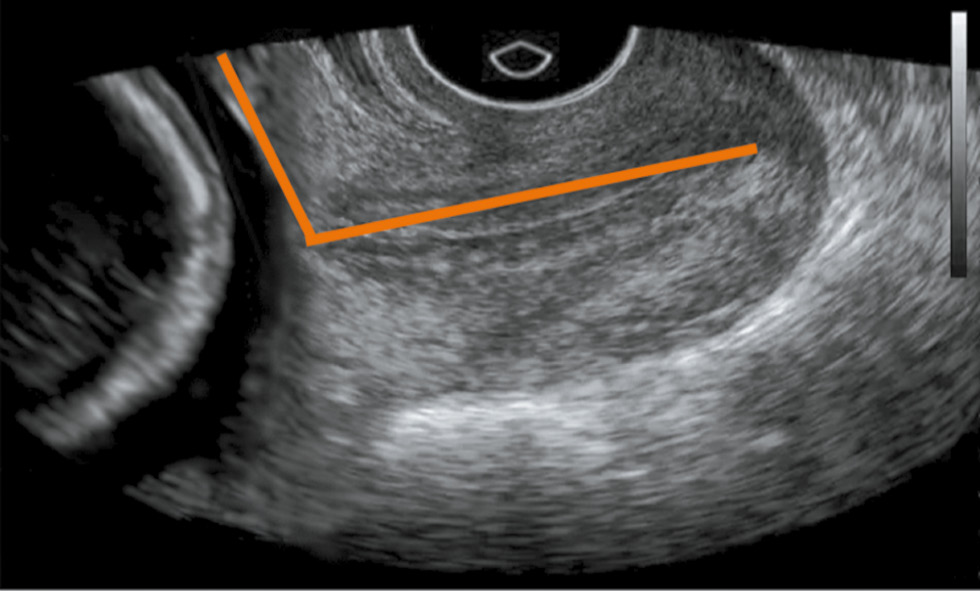

The mean SWS value in the area of the internal uterine orifice and the utero-cervical angle significantly differed in the studied groups (p < 0.05) (Table 2, Fig. 1, 2).

Fig. 1. Patient V., gestational age 28 weeks, utero-cervical angle - 106 °

Fig. 2. Patient L., gestational age 29 weeks, utero-cervical angle - 88 °

Among the pregnant women who subsequently had a preterm birth, already at 22–23 weeks of gestation, the mean SWS value in the internal uterine orifice was less than the normal values, whereas the value of the utero-cervical angle was higher compared to those who did not have preterm labor (p < 0.05). Indicators of the cervical length in the examined groups did not significantly differ.

Since the SWS values can be used to determine the elasticity of the tissue under study, a decrease in this indicator in pregnant women with subsequent preterm birth, as well as an increased utero-cervical angle, indicate cervical softening at 22–23 weeks of gestation; and at weeks 28–29, the SWS value continued to decrease, whereas the utero-cervical angle increased, which indicated cervical maturation and onset of preterm birth. Indicators, such as the mean SWS in the area of the internal uterine orifice and the utero-cervical angle, can be attributed to markers of preterm labor, which can be used to predict the development of labor.